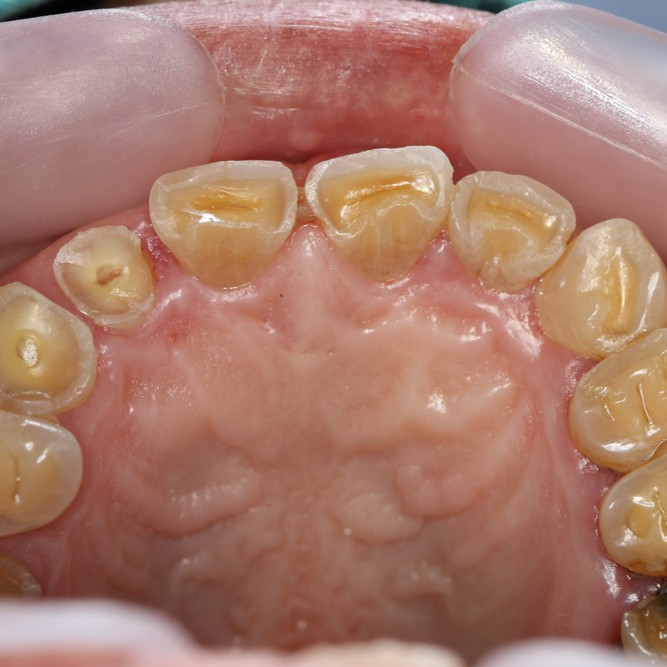

A 25 years old patient came to our attention – at the Section of Dentistry and Maxillofacial Surgery of University of Verona – asking for the alignment of the upper central incisors and closure of the diastemas present between all the anterior teeth of the upper arch. An alginate dental impression of both arches was taken and the intraoral and extraoral photographs required for planning the clinical case were captured. Esthetical parameters and occlusal relationship were registered.

All records were evaluated and a treatment plan was developed in agreement with functional and esthetical parameters, thereafter the treatment plan was submitted to patient in order to obtain her approval. With her informed written consent, the treatment began. Misalignment of upper central incisors was solved by using two palatal buttons positioned on elements 1.1 and 2.1 and applying a rotational force by means of metallic ligatures activated weekly for three months. After orthodontics, a diagnostic wax-up was made to better understand proportion and reshaping of restorations.

A digital previsualization of final result was therefore performed using Keynote software (iWork, Apple, Cupertino, California, USA) in order to face the esthetical requirements of our young patient. Moreover a silicon index was built, based on diagnostic wax-up, to help the direct restoration phase performed using Ceram.x composite resin (Ceram.x duo, Dentsply Sirona, Konstanz, Germany), as a result all the diastemas were closed and reshaping of elements from first left premolar to first right premolar was performed.